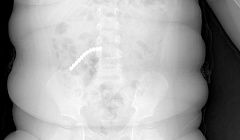

20 магнитных шариков проглотил двухлетний малыш в Улан-Удэ

Ребенку провели сложнейшую операцию.